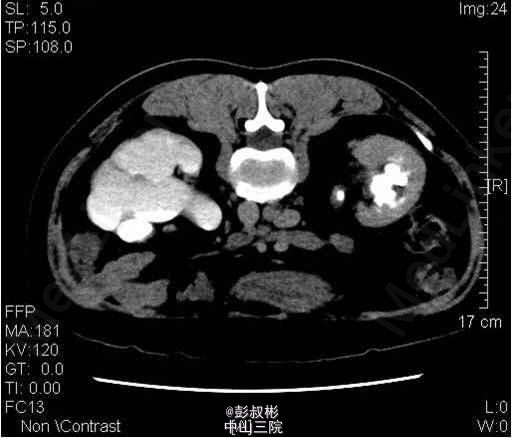

1、因“反复下腰部胀痛伴发热2月,加重10天” 入院。入院前最高体温39.5℃ ,外院检查尿隐血及尿白细胞3+,进一步行泌尿系B超显示双肾及左输尿管下段结石,左肾重度积液 。 2、既往史: 10年前因肾结石行体外冲击波碎石术,自诉术后恢复良好。 3、辅助检查:1) 血常规(抗炎后)、血生化(补钾后)、肝功、凝血、术前八项、胸片及心电图未见明显异常; 2) 尿常规:12.9 :尿液白细胞+++ 尿液红细胞++ 左肾造瘘液白细胞++ 左肾造瘘液红细胞++ 3) 真菌培养:无真菌生长 4) 肾功能:12.9: 肌酐5.68 mmol/L尿素氮: 186 nmol/L 5) 核素肾动态显像+GFR双血浆测定 1.右肾灌注、功能中度受损,右上尿路慢性梗阻。 2.左肾灌注、功能中度受损,左上尿路机械性梗阻。 灌注相:双肾于腹主动脉显影后2秒开始显影,放射性灌注明显减低(右肾明显低于左肾)。灌注曲线分析:双肾灌注峰明显减低。 功能相:右肾影稍增大,放射性摄取明显减低,放射性分布不均匀,可见多发放射性分布稀疏缺损区,放射性排泄缓慢。左肾增大,放射性摄取减低,放射性分布不均匀,可见多发放射性分布稀疏缺损区,放射性排泄缓慢,左肾盏见明显放射性滞留。半小时内膀胱可见放射性积聚。 肾图:右肾a段降低,b、c段融合为低水平延长型肾图。左肾a段降低,b、c段融合为持续上升型肾图。双血浆法肾小球滤过率(GFR)左肾为19.7ml/min,右肾GFR为17.9ml/min。 6) 双肾CTU平扫+增强螺旋扫描 1、左肾多发结石、重度积液、肾功能减退,左输尿管膀胱入口处结石,左侧输尿管炎症; 2、右肾多发结石、轻度积液,右肾功能减退,右肾盂及输尿管炎症。 4、诊断:双肾积脓 右肾铸形结石 左肾多发结石 左输尿管下段结石碎石术后 双肾功能减退 5、入院后处理:予以“舒普深” 3.0 Bid 抗感染,12-5 行“B超引导下经皮左肾穿刺造瘘术”,每日引流出约1500ml脓液。肾功能改善后于12-9行“左侧输尿管镜下钬激光碎石取石术”,术程顺利,术后予以舒普深3.0 Bid抗感染,体温正常。昨日下午行“B超引导下经皮右肾穿刺造瘘术”。